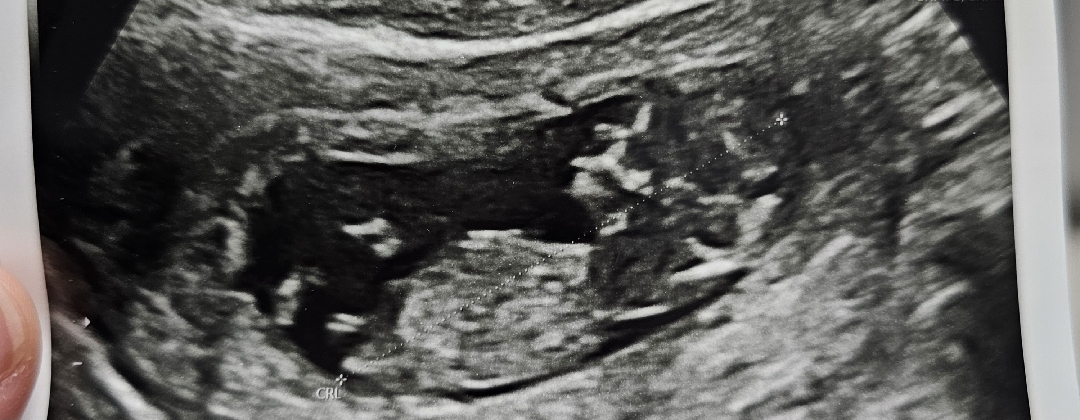

ㅎㅎ성별 너무 궁금하네요 11주차6일이에요 각도법보이시는분 댓글좀 부탁드려용